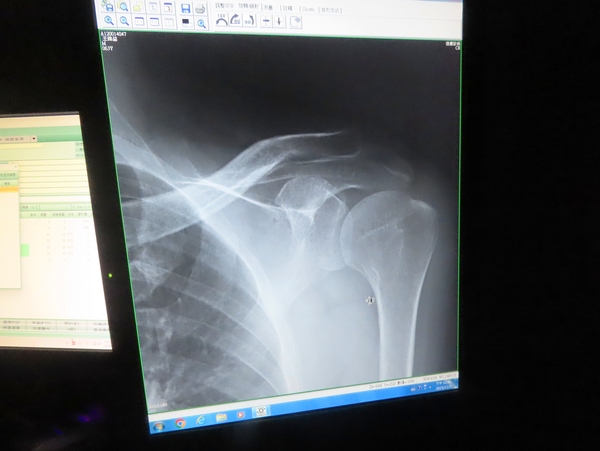

10:43 左手不能抬高,來佳德診所 (臺北市松山區健康路18號) 求診

佳德診所看診室

原來肩部活動與頸部脊椎有關

肩夾擠症候群(Shoulder Impingement Syndrome)是指當您抬高手臂時,肩膀的旋轉肌袖肌腱或肩峰下滑囊在肩峰(肩膀上方的骨頭凸起)下方被夾擠到,導致疼痛和發炎的現象。

左肩膀打了兩針 (大概是類固醇)